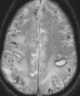

Gyriform cortical/subcortical T2 hypointensity

Acute cortical infarction

Subacute cortical infarction

Superficial siderosis